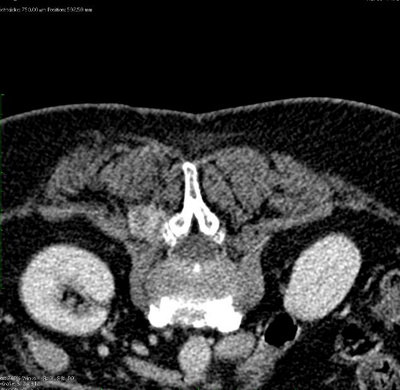

Schematische Darstellung des Kathetereingriffs im Rahmen einer Radioembolisation (SIRT) über die rechte Leiste.

Mittels Mikrokatheter erfolgt die selektive Behandlung durch Injektion der Mikrosphären.